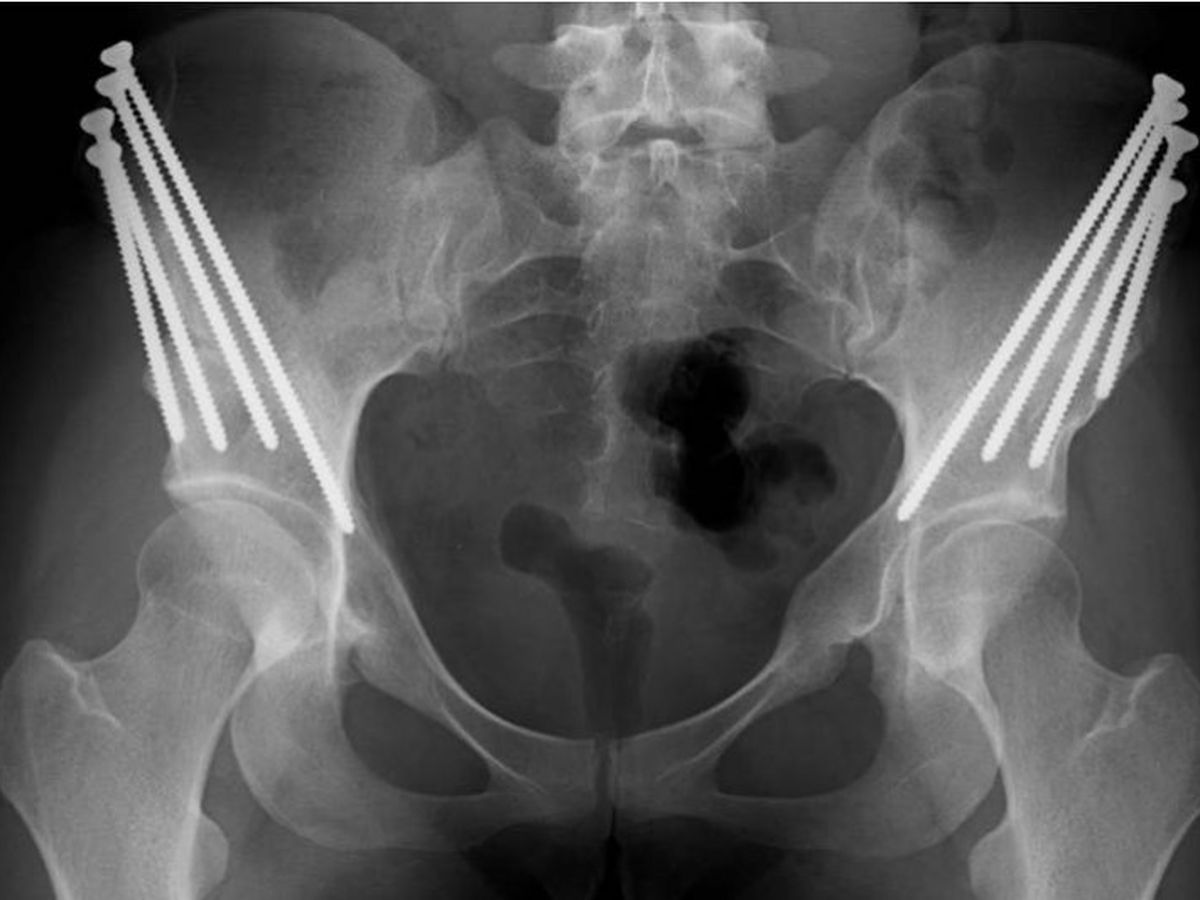

Sheila lives with hip dysplasia, a congenital disease that means her hip sockets do not cover her femur heads; this causes the joint to become painful, unstable, and completely dysfunctional over time. After years of successfully navigating her life and work as a professional dancer, teacher, and psychotherapist, Sheila's hips have finally given out; she is in need of multiple surgeries on both hips. Sheila will be undergoing 4-6 hip surgeries in the next year, including bilateral Periacetabular Osteotomies (PAO) and labral reconstructions. The PAO surgery is a major operation during which the surgeon breaks the pelvis in three places, rotates the acetabulum to cover the femur head, and then uses multiple screws to reassemble the joint. While this surgery will hopefully preserve Sheila's joint, the recovery process is long and arduous, involving inpatient hospitalization and several months of intensive physical therapy.